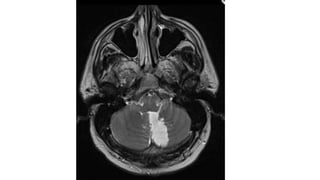

• #40 Resolution of syringomyelia (asterisk) after decompression of Chiari I malformation (white arrow).

Chiari malformation

• The brainstem and cerebellum are elongated downward into the

cervical canal - pressure on both the caudal midline cerebellum and

Duraplasty with pericranial graft

• The duraplasty - additional room for

cerebellar tonsils at the craniocervical

junction, while achieving closure of

dura and prevention of cerebrospinal

fluid leak.